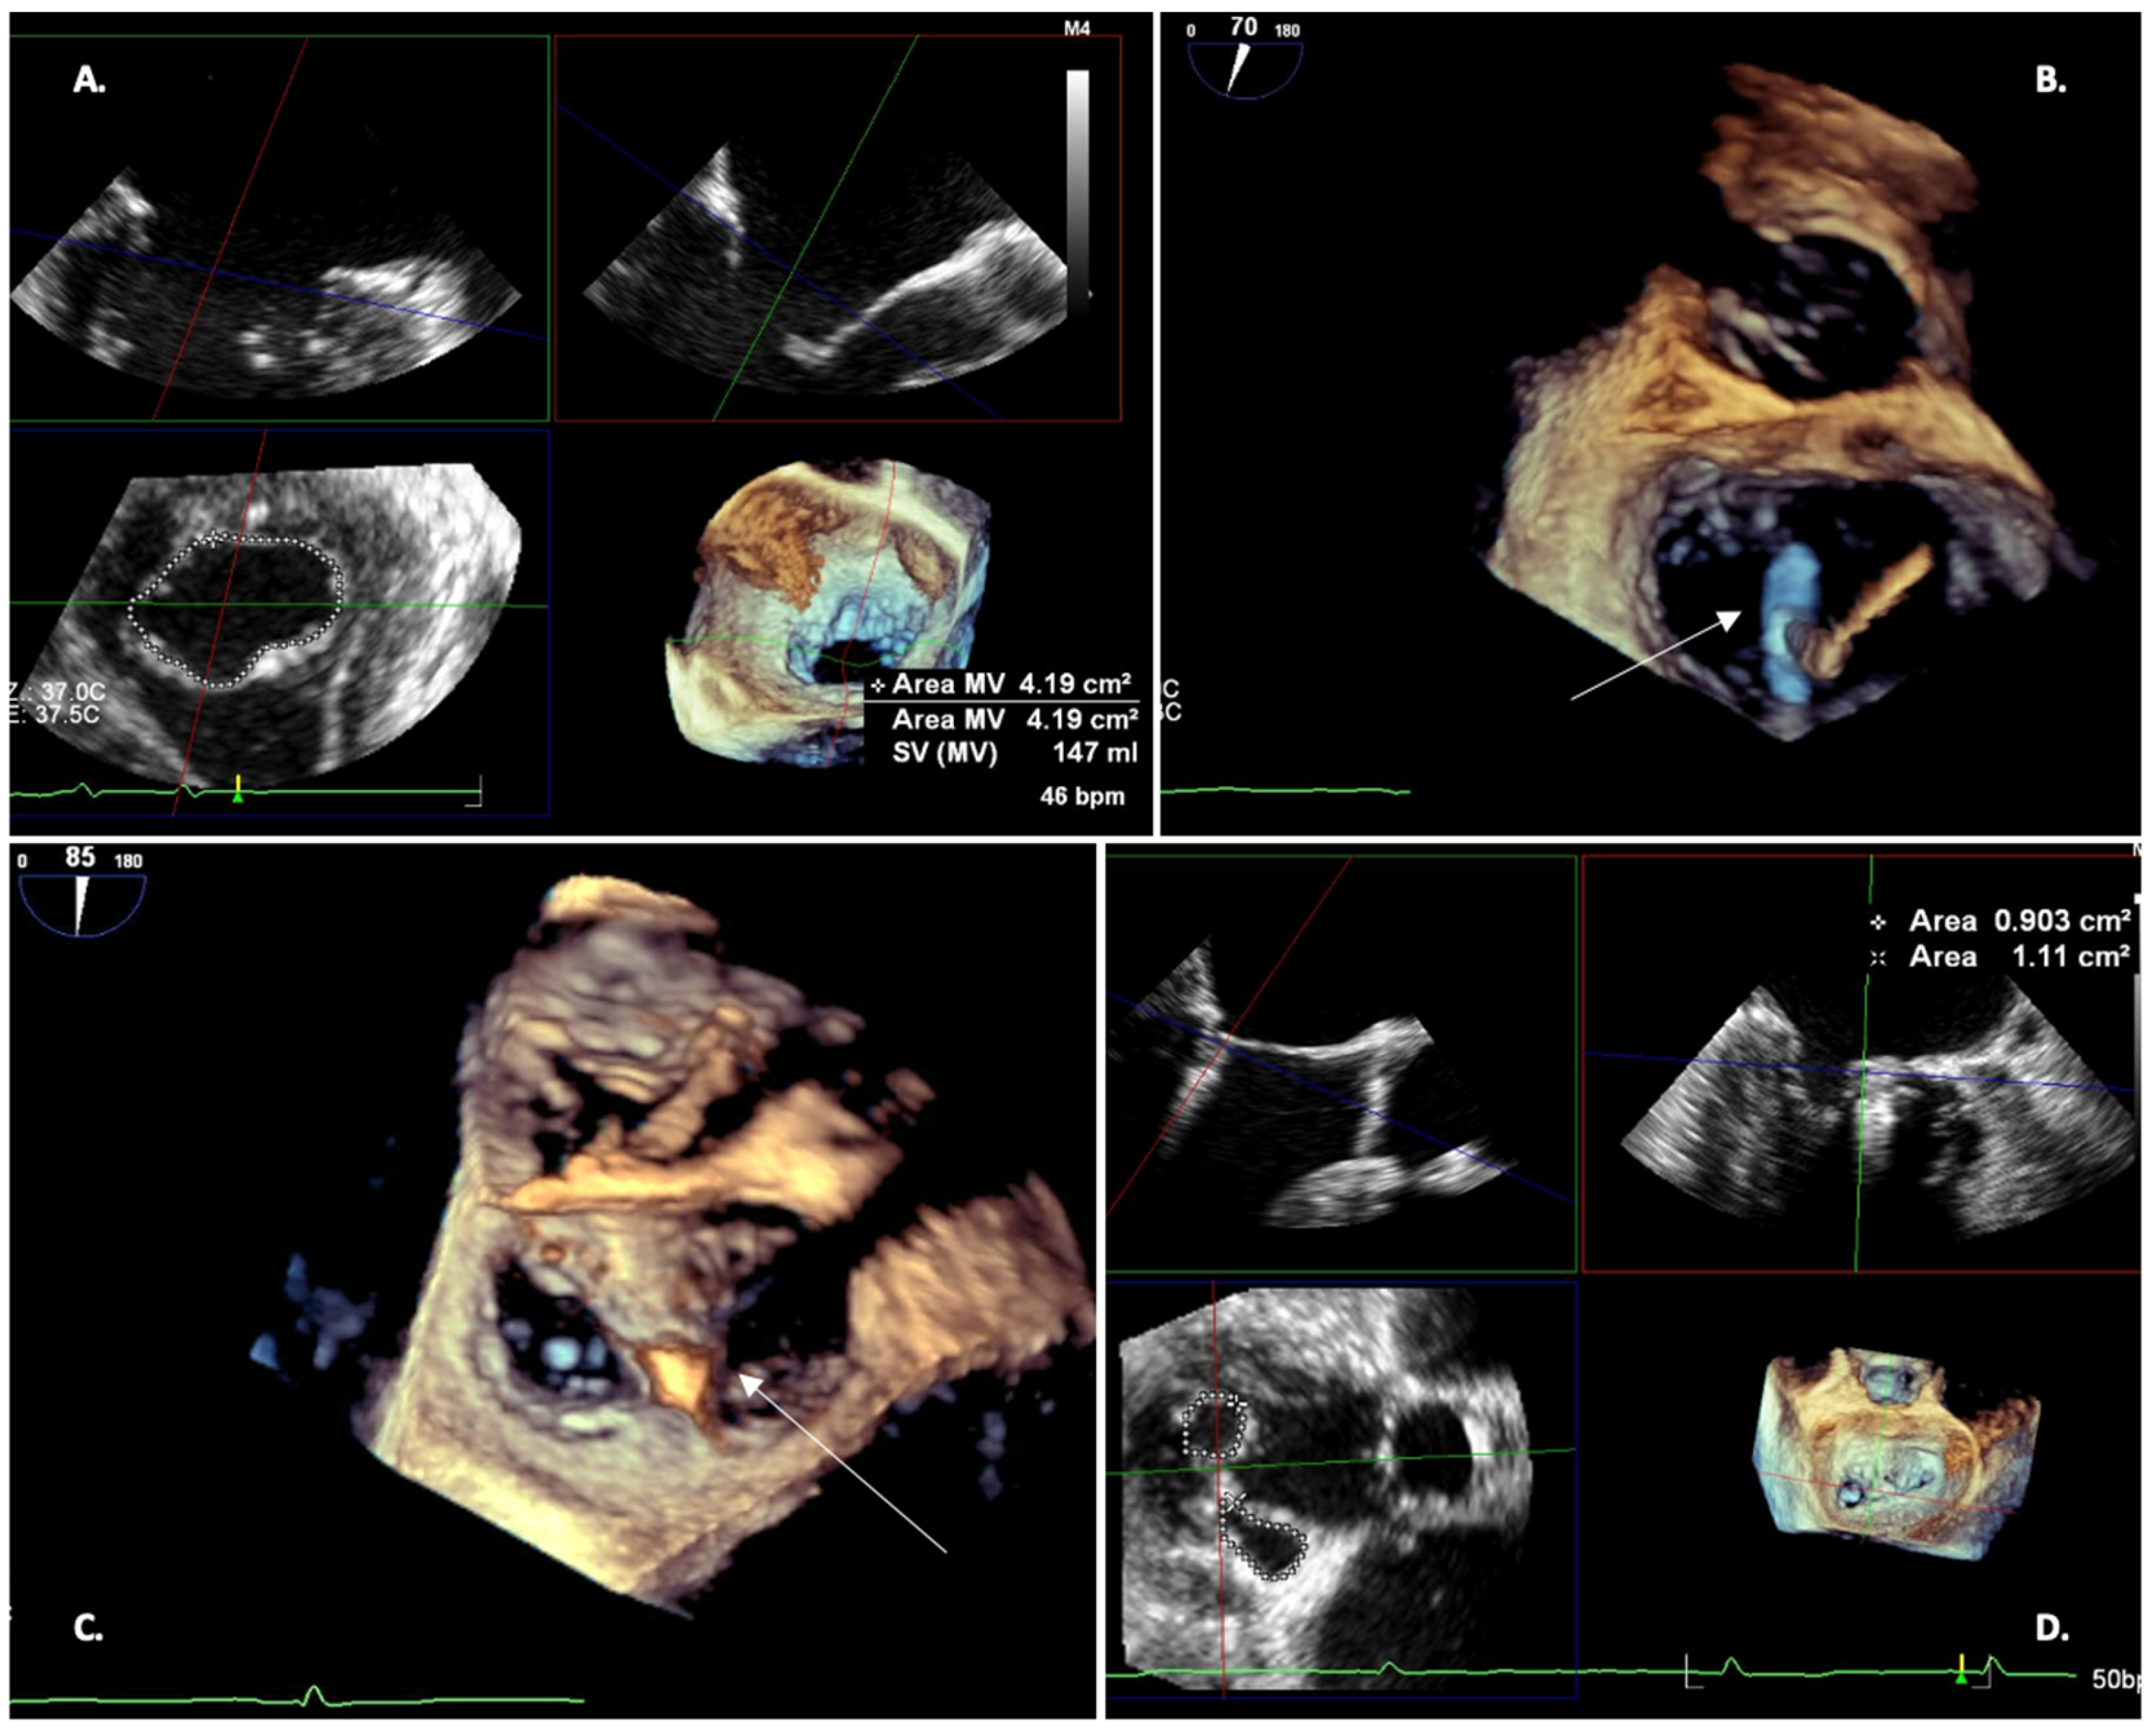

2.3. TEE 3D—Pre-Procedural Planning

- Reliably measure the mitral valve annulus, valve area, and tenting area

3. Procedural Phase

3.2. Clip Implantation

- The clip should be placed in the LA, over the center of the mitral valve, pointing toward the apex of the LV in the BI-COMMISSURAL view and above the coaptation line in the LVOT view. A 120–140° X-Plane view allows simultaneous projection. The trajectory must ensure perpendicularity to the plane of the mitral valve (MV). Once proper axial alignment is achieved on the target lesion, the device arms are unfolded and oriented perpendicular to the coaptation line. Off-axis grasping of the leaflets can lead to valve distortion which can lead to worsening mitral regurgitation or leaflet injury. The LVOT view should show both clip arms of the same length if the clip arm orientation is perpendicular to the coaptation line. The BI-COMMISSURAL view should show the clip as a bar, as this plane is oriented 90 degrees to the LVOT view and perpendicular to the clip arms.

- The clip should be oriented perpendicularly to the coaptation line; a 3D EN-FACE view helps to orientate when viewed from the LA. Clockwise rotation of the system causes clockwise rotation of the clip arms; conversely, when viewed from the LV, counterclockwise rotation of the system results in clockwise rotation of the clip arms.

- Correct flap insertion and clip location at the origin of the MR jet should be ensured. The LVOT/4CH view can confirm that mitral leaflets are adequately captured, whilst the BICOMMUSSUAL view is used to ensure that the flap on each side bisects the clip. Finally, an EN-FACE 3-D view shows the presence of a stable double orifice and the reduction of the MR jet.

- After adequate insertion of the flaps at 60 degrees of clip closure has been confirmed, the clip should be slowly closed further until the flaps are covered. The degree of MR reduction should be evaluated with color Doppler in all TEE views. Once the result is satisfactory, the device is detached from the delivery system Figure 6.